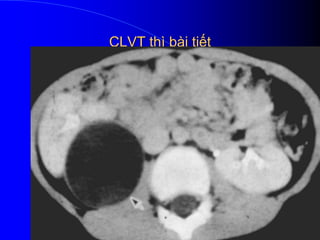

- CLVT phaït hiãûn khaï nhaûy > 75% trhåüp, våïi âiãöu

kiãûn tiãm TCQ nhanh vaì xoàõn äúc nhiãöu thç (thç voí

tháûn vaì thç baìi tiãút muäün):

+ Tháûn tàng thãø têch do phuì viãm.

+ Vuìng täøn thæång khäng phán biãût tuyí voí (↓ tè

troüng).

Thç baìi tiãút muäün sau vaìi giåì vuìng bãûnh tàng

tè troüng so våïi nhu mä laình do caïc äúng tháûn

bë tàõc ngáúm TCQ cháûm (phán biãût: VTBT äø,

aïp xe tháûn, u tháûn.

Gáön âáy, våïi kyî thuáût CLVT xoàõn äúc thç

muäün (thç mä tháûn hoàûc thç baìi tiãút) seî tháúy

hçnh aính daíi hoàûc hçnh chãm khäng âäöng

nháút, tháûn coï hçnh chàõp vaï.

CLVT thì bài tiết